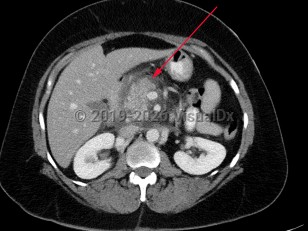

Chest pain, Pleural effusion, 50-59 year old Female

Pleural effusionPleural effusion

Hemothorax

Acute pancreatitis